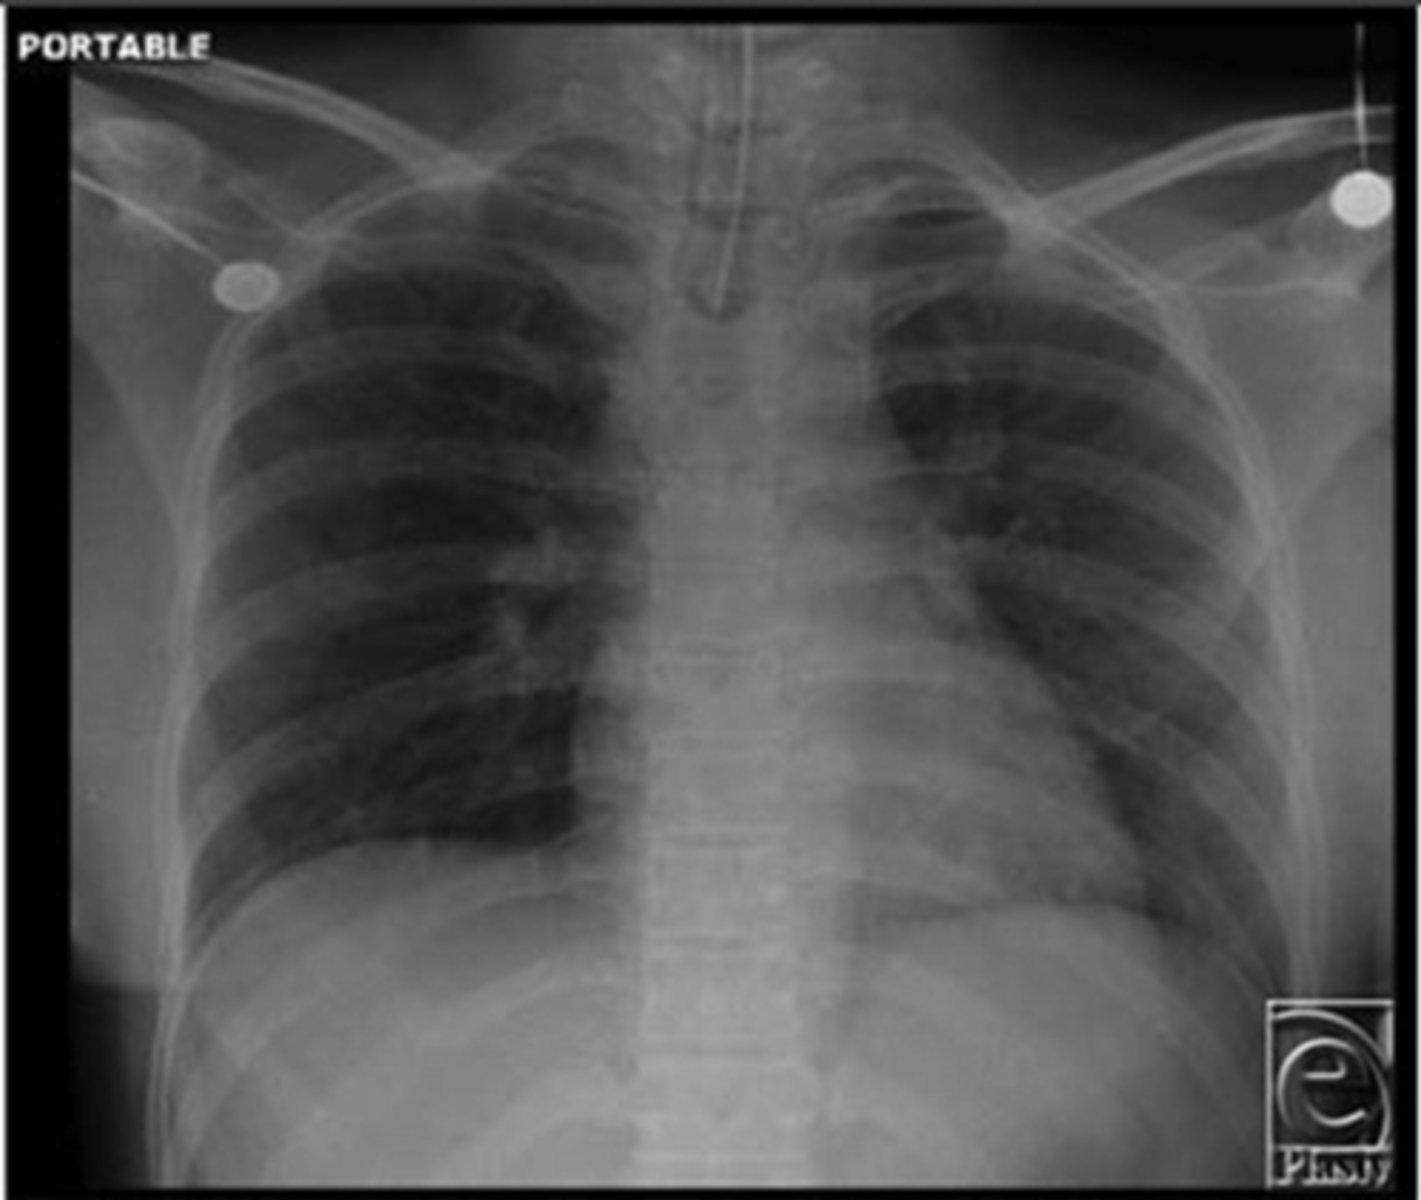

PA view (heart is normal size, patient is standing)

Which view is this?